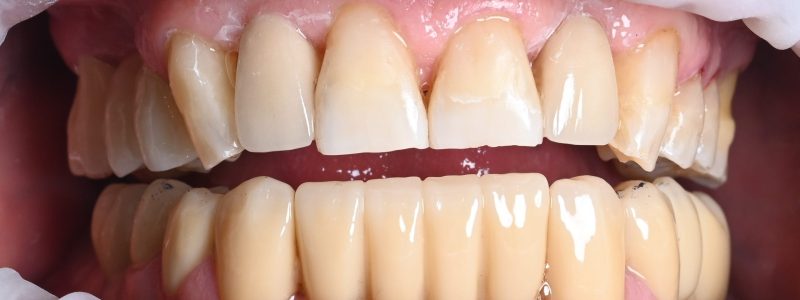

Redarea funcției masticatorii și estetice prin restaurări complexe cu ajutorul coroanelor pe implanturi tip FP1, cu aspect natural si sănătos al gingiei.

Montarea lucrării provizorii fixe

În aceeași zi sau la scurt timp după intervenție, se montează lucrarea provizorie – zâmbești din nou imediat.

Lucrarea finală definitivă

După perioada de osteointegrare (3–6 luni), se montează lucrarea definitivă, realizată individual, cu estetică naturală și durabilitate ridicată.